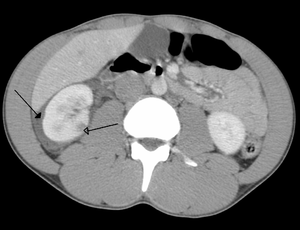

Abdominal trauma resulting in a right kidney contusion (open arrow) and blood surrounding the kidney (closed arrow) as seen on CT. | |

Kidneys

The kidneys may also be injured; they are somewhat but not completely protected by the ribs.[7] Kidney lacerations and contusions may also occur.[13] Kidney injury, a common finding in children with blunt abdominal trauma, may be associated with bloody urine.[13] Kidney lacerations may be associated with urinoma or leakage of urine into the abdomen.[6] A shattered kidney is one with multiple lacerations and an associated fragmentation of the kidney tissue.[6]